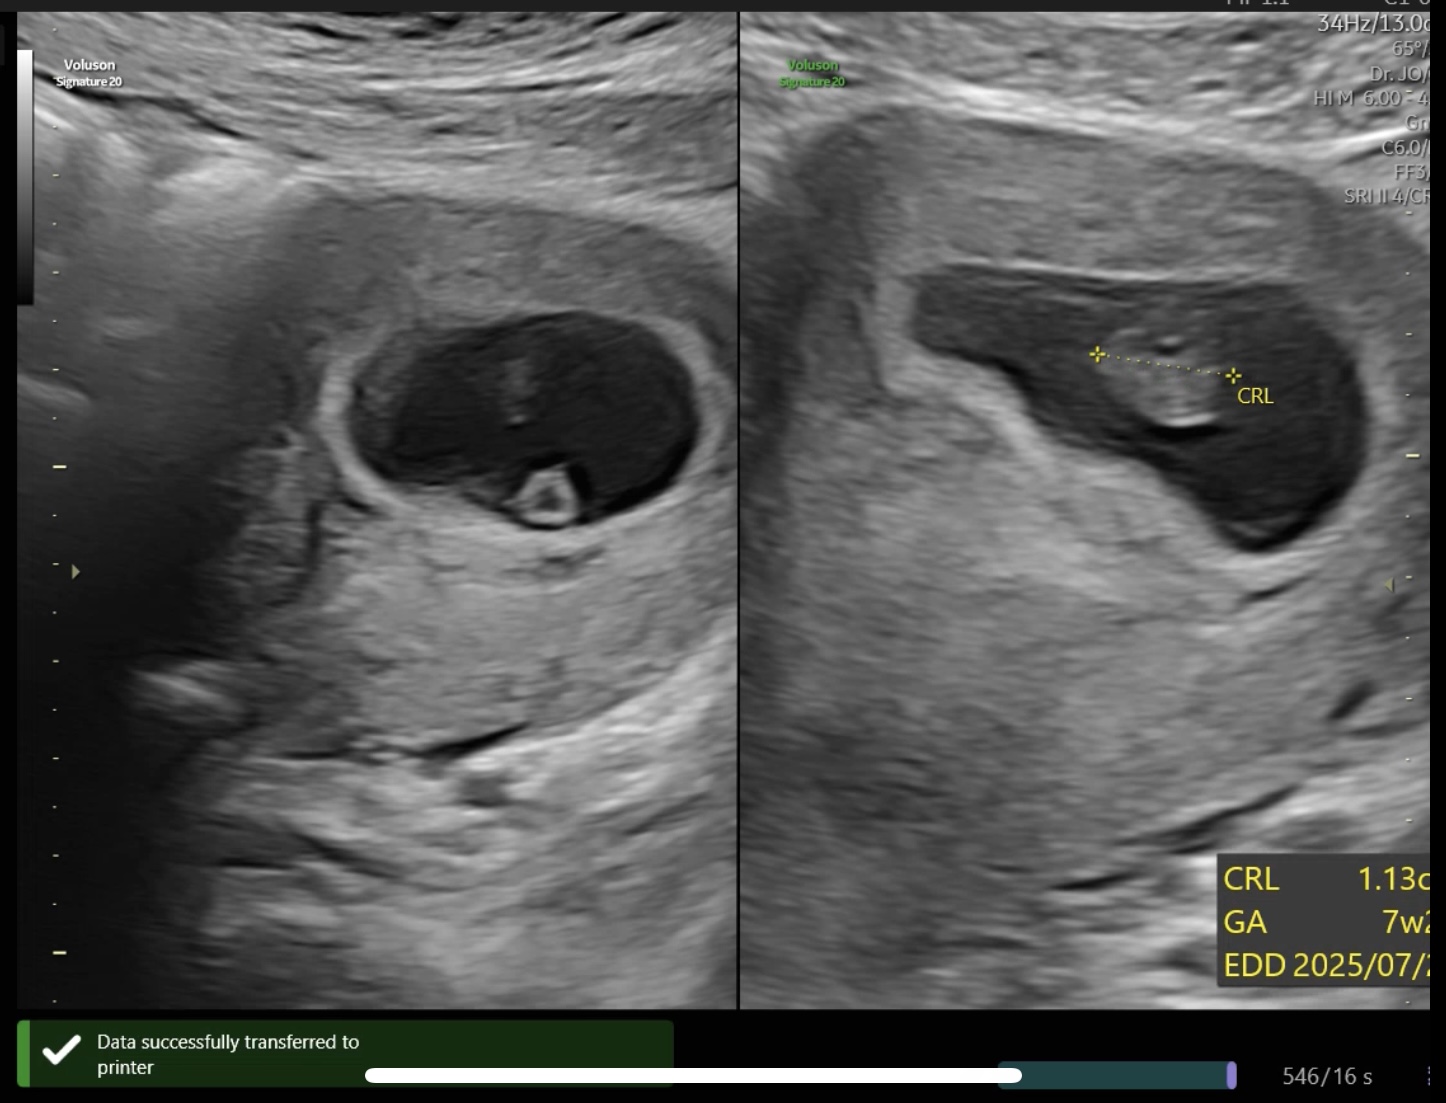

7주 2일차 산부인과 진료에서는

아기의 심장 소리를 처음 들었다.

주수에 맞게 규칙적인 박동이 확인되었고,